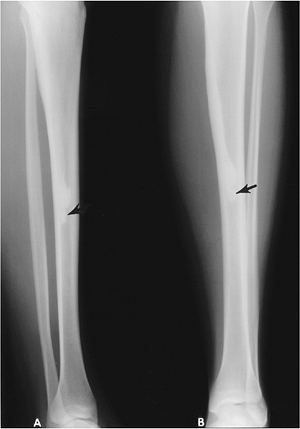

FIGURE 15-4 Melorheostosis. Lateral (A) and AP (B)

views of the tibia showing sclerosis along the posteromedial cortex resembling “dripping candle wax” that ends in the mid-diaphysis (arrow). |

FIGURE 15-5

Melorheostosis. Standing views of the knees showing sclerosis and cortical thickening that crosses the joint into the soft tissues. The tibia also is involved. |